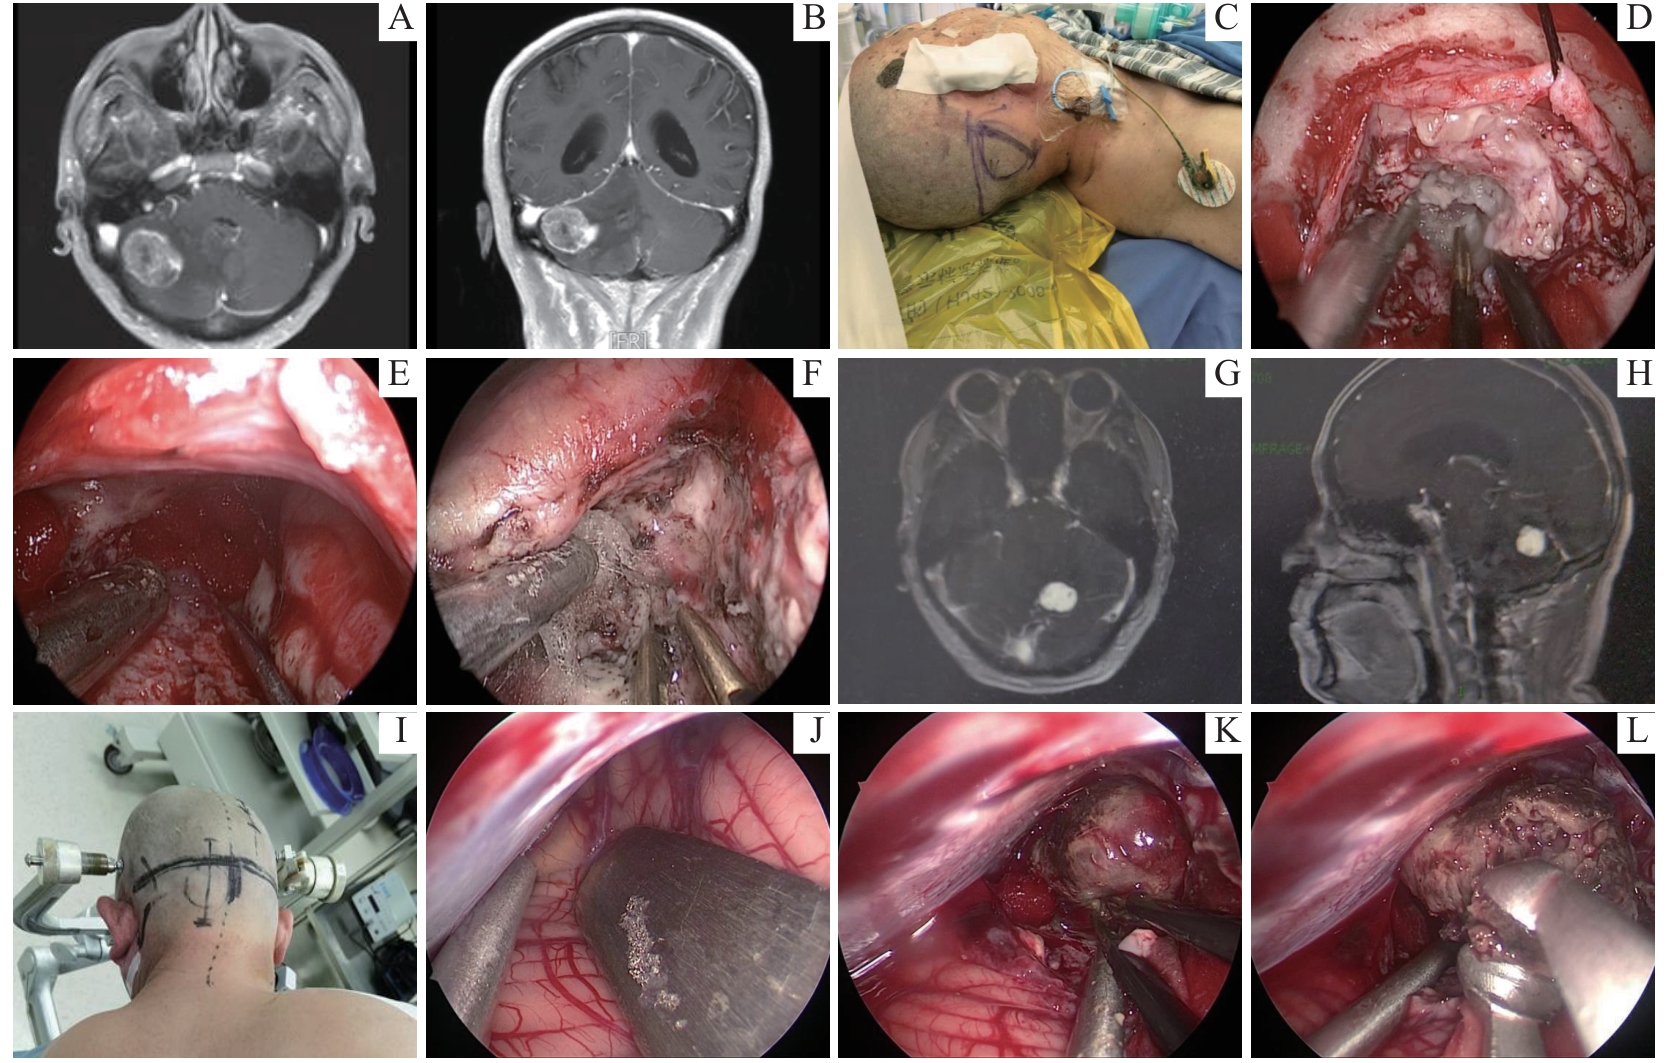

Application of full-neuroendoscopic technique in surgical treatment of posterior cranial fossa lesions

Objective ·To investigate the application effects and benefits of full-neuroendoscopic technique in the surgical treatment of posterior cranial fossa lesions. Methods ·A retrospective analysis was conducted on the clinical data of 105 patients with posterior cranial fossa lesions who underwent surgery using full-neuroendoscopic techniques at the Department of Neurosurgery, Renji Hospital, Shanghai Jiao Tong University School of Medicine, between January 2021 and December 2023. The data included patients′ gender, age, lesion locations, nature of lesions, surgical procedures, and postoperative recovery. Follow-up with contrast-enhanced MRI was performed one month postoperatively, with subsequent follow-ups every three months on average, depending on the nature of the lesions. Results ·Among the 105 patients, there were 45 males with an average age of (56±17) years and 60 females with an average age of (62±12) years. Lesions were predominantly located in the cerebellopontine angle area (78 cases), with others in the petrous bone area (7 cases), cerebellum (10 cases), and brainstem (10 cases). The nature of lesions included vestibular schwannoma (11 cases), meningioma (7 cases), glioma (7 cases), brain metastases (7 cases), hemangioblastoma (6 cases), cyst (1 case), and neuropathic conditions such as trigeminal neuralgia (43 cases), hemifacial spasm (22 cases), and glossopharyngeal neuralgia (1 case). All patients successfully underwent resection or biopsy of their lesions or microvascular decompression under full-neuroendoscopy. The follow-up period ranged from 3 months to 3 years. Enhanced MRI confirmed complete resection in 34 tumor cases (87.2%), near-total resection in 3 cases (7.7%), and biopsy in 2 cases (5.1%). Three deaths occurred during follow-up. Among the patients with vascular neuropathic diseases, two with trigeminal neuralgia experienced incomplete pain relief postoperatively. The resolution rates for hemifacial spasm and glossopharyngeal neuralgia were 100%. Postoperative complications occurred in 3 cases, with 2 cases of hydrocephalus that were managed with ventriculoperitoneal shunting, and 1 case of poor wound healing. Conclusion ·Full-neuroendoscopic technique demonstrates potential in the surgical treatment of posterior cranial fossa lesions.